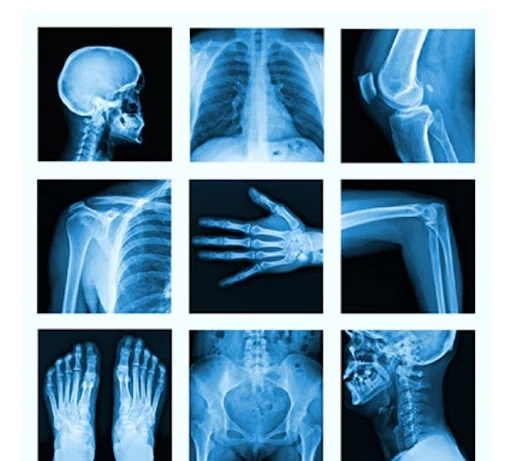

1. X-rays.

Initial imaging to detect anomalies in the bone.